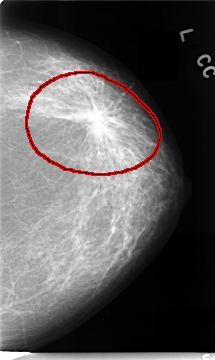

C_0089_1.LEFT_MLO

FILE: C_0089_1.LEFT_MLO.OVERLAY

TOTAL_ABNORMALITIES 1

ABNORMALITY 1

LESION_TYPE MASS SHAPE IRREGULAR MARGINS SPICULATED

ASSESSMENT 5

SUBTLETY 5

PATHOLOGY MALIGNANT

TOTAL_OUTLINES 1

BOUNDARY